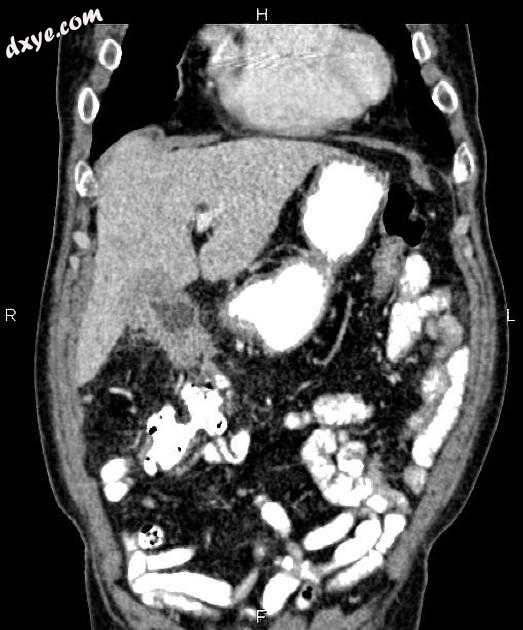

冠状C +门静脉期

胆囊体和底存在不对称的壁厚增加。邻近的肝实质中存在轻度异质增强,提示局部浸润。另外,在相邻区域观察到脂肪滞留和肿瘤沉积。

经路径证实的胆囊腺癌。

在成像时,它们可表现为局灶性腔内肿块,局灶性或弥漫性胆囊壁不规则增厚,或大块病变,可代替整个胆囊。描绘出具有一定程度侵犯邻近结构或转移性疾病的肿瘤并不少见。